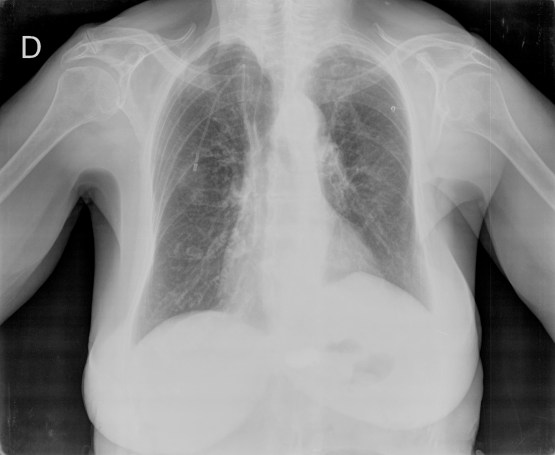

CASO: sospecha de neumonía.

Hallazgos:

- En un principio podríamos decir que existe un aumento de densidad retrocardiaco que podría ser compatible con condensación neumónica a dicho nivel, sin embargo estamos ante una placa poco inspirada, lo cual puede llevarnos a cometer errores diagnósticos.

- Se recomendó volver a realizar la radiografía, observar a continuación:

Ya no se observa el aumento de densidad retrocardiaco, la placa es normal.

INSPIRACIÓN: Una placa bien inspirada es aquella en la que se observar 6-7 arcos costales anteriores o 10-11 arcos costales posteriores. Lo contrario puede producir imágenes falsas de condensaciones o de seudocardiomegalia.